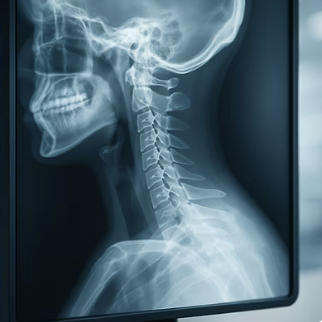

반면, '경추성 두통'은 이름 그대로 그 원인이 머리가 아닌 '목(경추)'에 있습니다. 잘못된 자세나 퇴행성 변화로 인해 목뼈나 주변 근육, 인대가 손상되면서, 그 통증이 신경을 타고 머리로 뻗쳐나가는 '구조적인' 문제입니다. 마치 벽 속의 전선이 잘못되어 엉뚱한 곳의 전등이 깜빡이는 것과 같죠.

하지만 '경추성 두통'은 이러한 소화기 증상이나 감각 예민 증상은 거의 없습니다. 대신, 두통이 시작될 때 거의 항상 '목과 어깨의 뻣뻣함'이나 '통증'을 동반합니다. 손으로 목 뒤나 어깨를 눌렀을 때 유독 아픈 지점이 있거나, 고개를 돌릴 때 움직임이 부자연스럽고 아프다면, 그 두통의 범인은 목에 있을 확률이 매우 높습니다.

반면, '경추성 두통'의 통증은 울리는 느낌보다는 '뻐근'하거나 '묵직'하게 조여오는 느낌에 가깝습니다. 통증은 주로 뒷목이나 뒤통수에서 시작되어 정수리나 이마, 눈 주변으로 뻗쳐나가는 양상을 보입니다. 움직인다고 해서 통증이 급격히 심해지기보다는, 꾸준히 지속되는 둔한 통증인 경우가 많습니다.